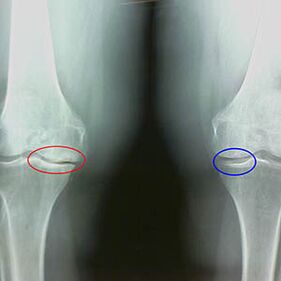

Caractéristiques x-Arrivée de la deuxième phase du genou illégal:

- Les bords pointus des tubercules inter-scrip sur le tibia, où le ligament en forme de croix est attaché;

- rétrécissement de l'écart articulaire du côté médial;

- Les bords pointus des os condyli sur les côtés médiaux, moins souvent en latérale, selon le développement du valgus ou de la déformation articulaire varor.

Pour la deuxième phase de Larsen Le rétrécissement de l'écart articulaire de plus de 50% est caractéristique, mais cela ne peut être contrôlé que dans la dynamique ou la comparaison avec une articulation différente.